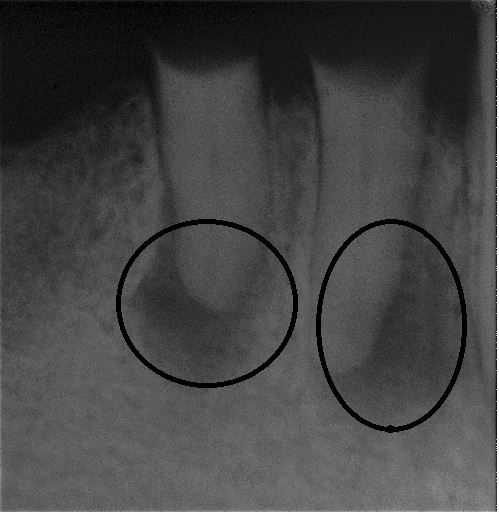

Fallbeispiel für eine große Entzündung an der Wurzel

Wurzel nach erfolgreicher Behandlung 2 Monate später schon fast ausgeheilt